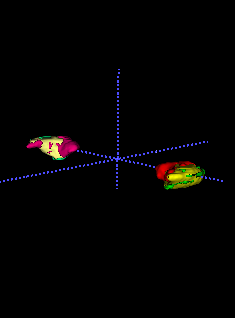

In Chapter 6, we propose an end-to-end, atlas-free 3D convolutional deep learning framework for fast and fully automated whole-volume HaN anatomy segmentation [115]. Our deep learning model, called AnatomyNet, segments OARs from head and neck CT images in an end-to-end fashion, receiving whole-volume HaN CT images as input and generating masks of all OARs of interest in one shot. AnatomyNet is built upon the popular 3D U-net architecture, but extends it in three important ways: 1) a new encoding scheme to allow auto-segmentation on whole-volume CT images instead of local patches or subsets of slices, 2) incorporating 3D squeeze-and-excitation residual blocks in encoding layers for better feature representation, and 3) a new loss function combining Dice scores and focal loss to facilitate the training of the neural model. These features are designed to address two main challenges in deep-learning-based HaN segmentation: a) segmenting small anatomies (i.e., optic chiasm and optic nerves) occupying only a few slices, and b) training with inconsistent data annotations with missing ground truth for some anatomical structures. We collect 261 HaN CT images to train AnatomyNet, and use MICCAI Head and Neck Auto Segmentation Challenge 2015 as a benchmark dataset to evaluate the performance of AnatomyNet. The objective is to segment nine anatomies: brain stem, chiasm, mandible, optic nerve left, optic nerve right, parotid gland left, parotid gland right, submandibular gland left, and submandibular gland right. Compared to previous state-of-the-art results from the MICCAI 2015 competition, AnatomyNet increases Dice similarity coefficient by 3.3% on average. AnatomyNet takes about 0.12 seconds to fully segment a head and neck CT image of dimension , significantly faster than previous methods. In addition, the model is able to process whole-volume CT images and delineate all OARs in one pass, requiring little pre- or post-processing. We demonstrate that our proposed model can improve segmentation accuracy and simplify the auto-segmentation pipeline. These contributions are released as an open-source software package called AnatomyNet, which is publicly available555https://github.com/wentaozhu/AnatomyNet-for-anatomical-segmentation. Portions of this chapter were published as part of [115].

- [121] W. Zhu and X. Xie. Adversarial deep structural networks for mammographic mass segmentation. arXiv:1612.05970, 2016.